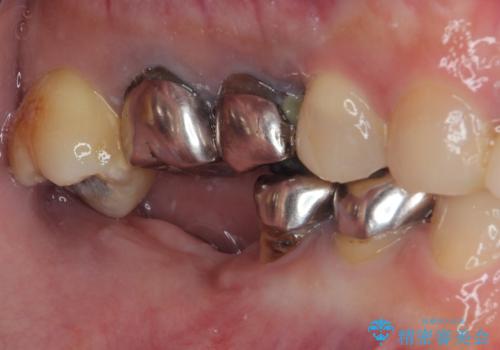

- 「歯を抜いたので、インプラントを入れてほしい」という主訴で来院された患者様です。

他院で歯根破折により抜歯をしたとのことでした。

CTにより残存骨量を確認しインプラント埋入を行っていくこととしました。

今後手前の根管治療を行っている歯が歯根破折を起こして抜歯になる可能性を想定して手前の歯に平行にインプラント埋入を行っています。